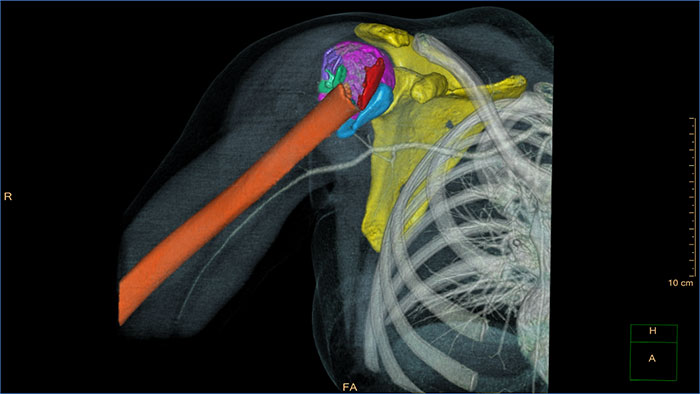

Streamlined modeling workflow

Allows to view volumetric images of anatomical structures, perform segmentation, edit and combine segmented elements (tissues) into a 3D model.

*3D models are not intended for diagnostic use.